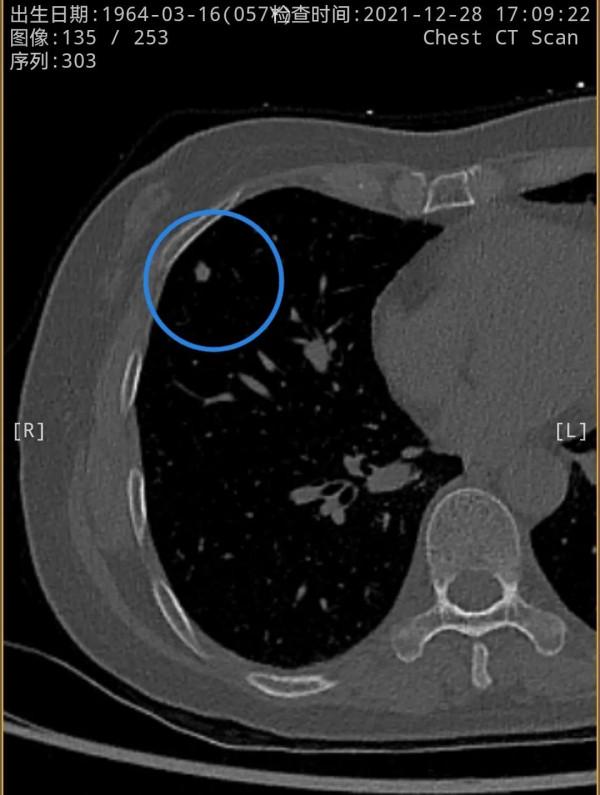

我們先來看2021年12月的,右肺多發實性結節,邊緣相對平直,膨脹性不明顯,紅色圈起來的主病灶周邊一圈密度高,中間密度低,還有點狀高密度,考慮肉芽腫性炎伴壞死(區域性纖維鈣化),次病灶藍色圈起來的形態也是類似的,骨窗看也是中間密度低,而周邊一圈密度高。那麼再來看2019年時是如何的呢?假如是惡性,應該有進展。但我們閱片後發現並沒有大的變化,由於掃描條件不同,中間密度低在平掃上不明顯,紫紅圈起來的和綠色圈起來的分別對應主病灶和次病灶。但當時有區域性靶掃描,結果形態與2年後的沒什麼區別,當時也已經是周邊一圈密度高,而中間密度低且均勻。所以此兩灶可基本認定為肉芽腫性炎伴壞死,可安全隨訪。最好半年查一次(因為正常沒結節也一年查一次呢)。